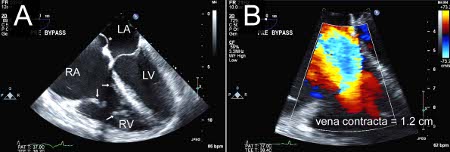

Severe tricuspid regurgitation due to carcinoid valvular disease. A. Systolic frame from mid-oesophageal 4 chamber view. Note thickened tricuspid leaflets, but also retracted and thickened chordae, typical of advanced carcinoid valvular disease (arrows). The right ventricle and right atrium are enlarged. The atrial septum is deviated to the left, demonstrating right atrial pressure is higher than left atrial pressure (asterisk). B. Colour Doppler demonstrating severe tricuspid regurgitation. Vena contracta measured 1.2 cm, consistent with the coaptation gap on 2D images and virtually free flow between the right ventricle and right atrium.

From the collection of Sorin V. Pislaru, Mayo Clinic